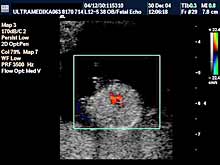

A) I trimestar do 14

nedelje gestacije

(3 meseca + 2 nedelje)

Indikacije za ultrazvučni pregled:

- Izostanak menstruacije, procena vitalnosti rane trudnoće,

procena materične i/ili postojanje vanmaterične trudnoće.

(Od 4-7 nedelje gestacije, ili prva 2 meseca od prvog dana zadnje

menstruacije).

- GENETSKI SONOGRAM (2 - 3 ½ meseca):

- Otkrivanje ultrazvučnih markera na postojanje hromozomskih

anomalija ploda (SKRINING na ANEUPLOIDIJE). Ovaj genetski sonogram

treba uraditi dva puta u intervalu od 9 do 14 nedelje gestacije uz

biohemijsku proveru iz krvi trudnice nakon tačne ultrazvučne procene

veličine ploda. Genetski sonogram sam isključuje oko 88% trizomija,

a udružen sa biohemiskim analizama se isključuje oko 98%

aneuploidija.

- Prva procena i otkrivanje krupnih anatomskih anomalija ploda

koje ne moraju pratiti hromozomske anomalije.

- Prva procena posteljične cirkuacije Broandband - CD

- Pregled materice i organa male karlice kao i organa abdomena

trudnice.